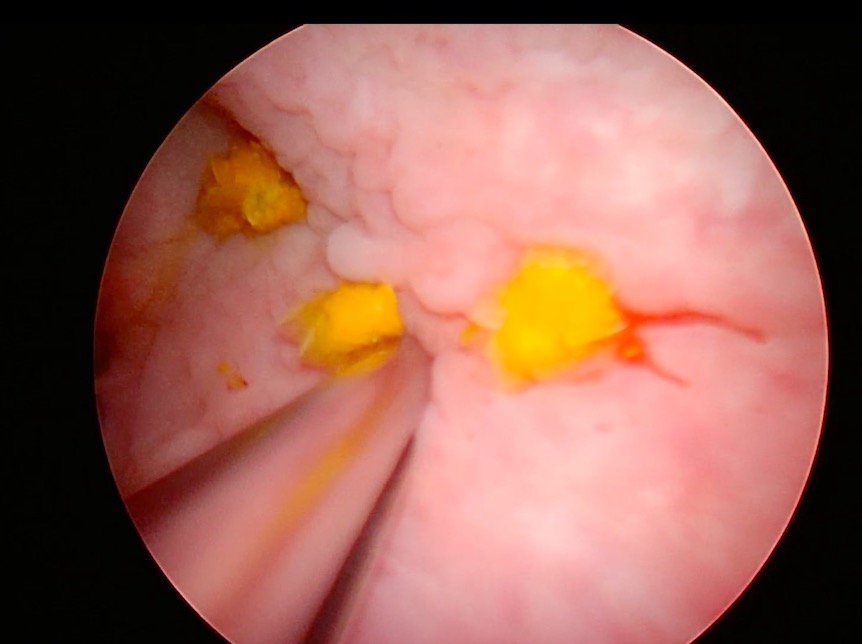

膀胱内の結石を腹腔鏡で見つつ、鉗子で摘出している写真です。

結石の取り残しがないか最終チェックしている写真です。

生理食塩水を尿道カテーテルから入れていき、ある程度の膀胱の張りを保ちつつ、鉗子やサクションを用いて膀胱結石を摘出していきます。最後に膀胱内をカメラでチェックし、尿道カテーテルを抜去していきながら尿道へカメラを進めていき、

膀胱内、尿道内に結石がないことを確認した後、膀胱を縫合します。